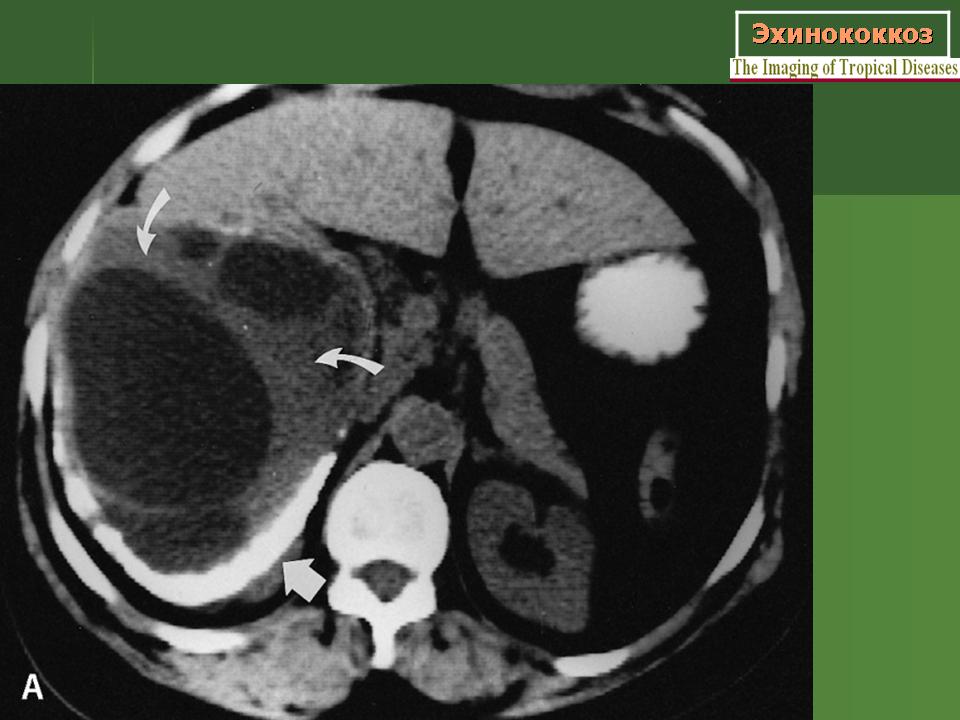

Эхинококкоз ( Ecninococcus unilocularis )

Figure 15: Echinococcus cyst in the liver, contrast enhanced CT